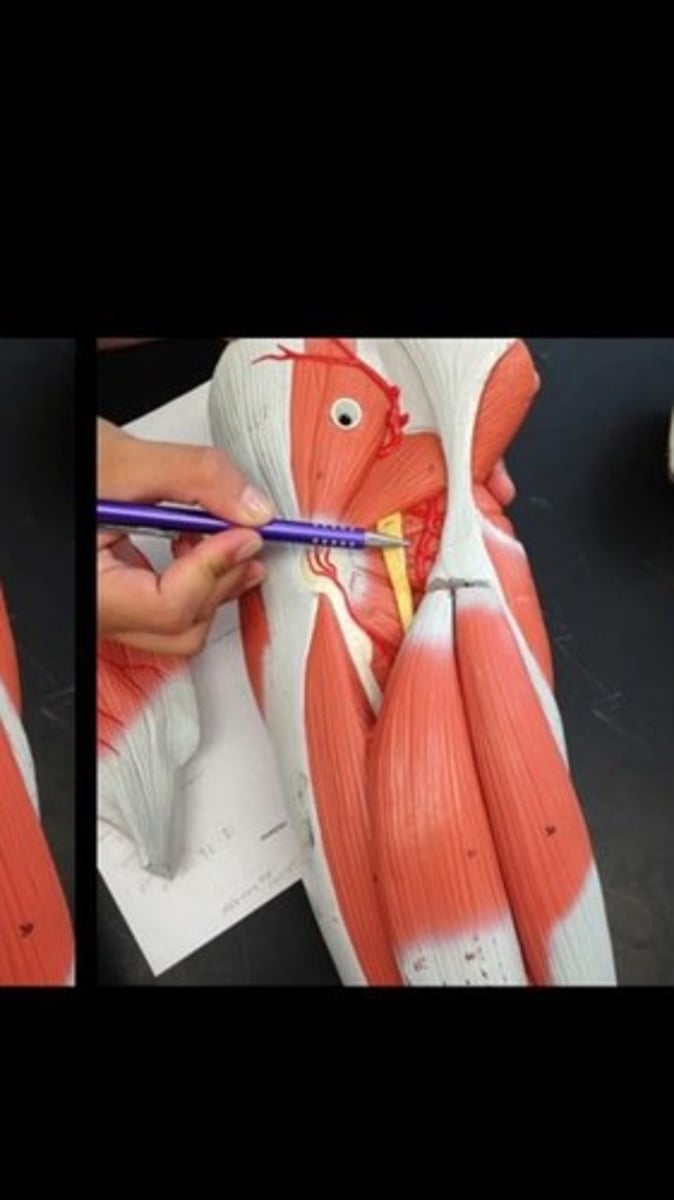

Skeletal muscle terms and structure

114 Terms

Sartorius

Iliopsoas

Adductor longus

Gracilis

Adductor magnus

Rectus femoris

Vastus lateralis

Vastus medialis